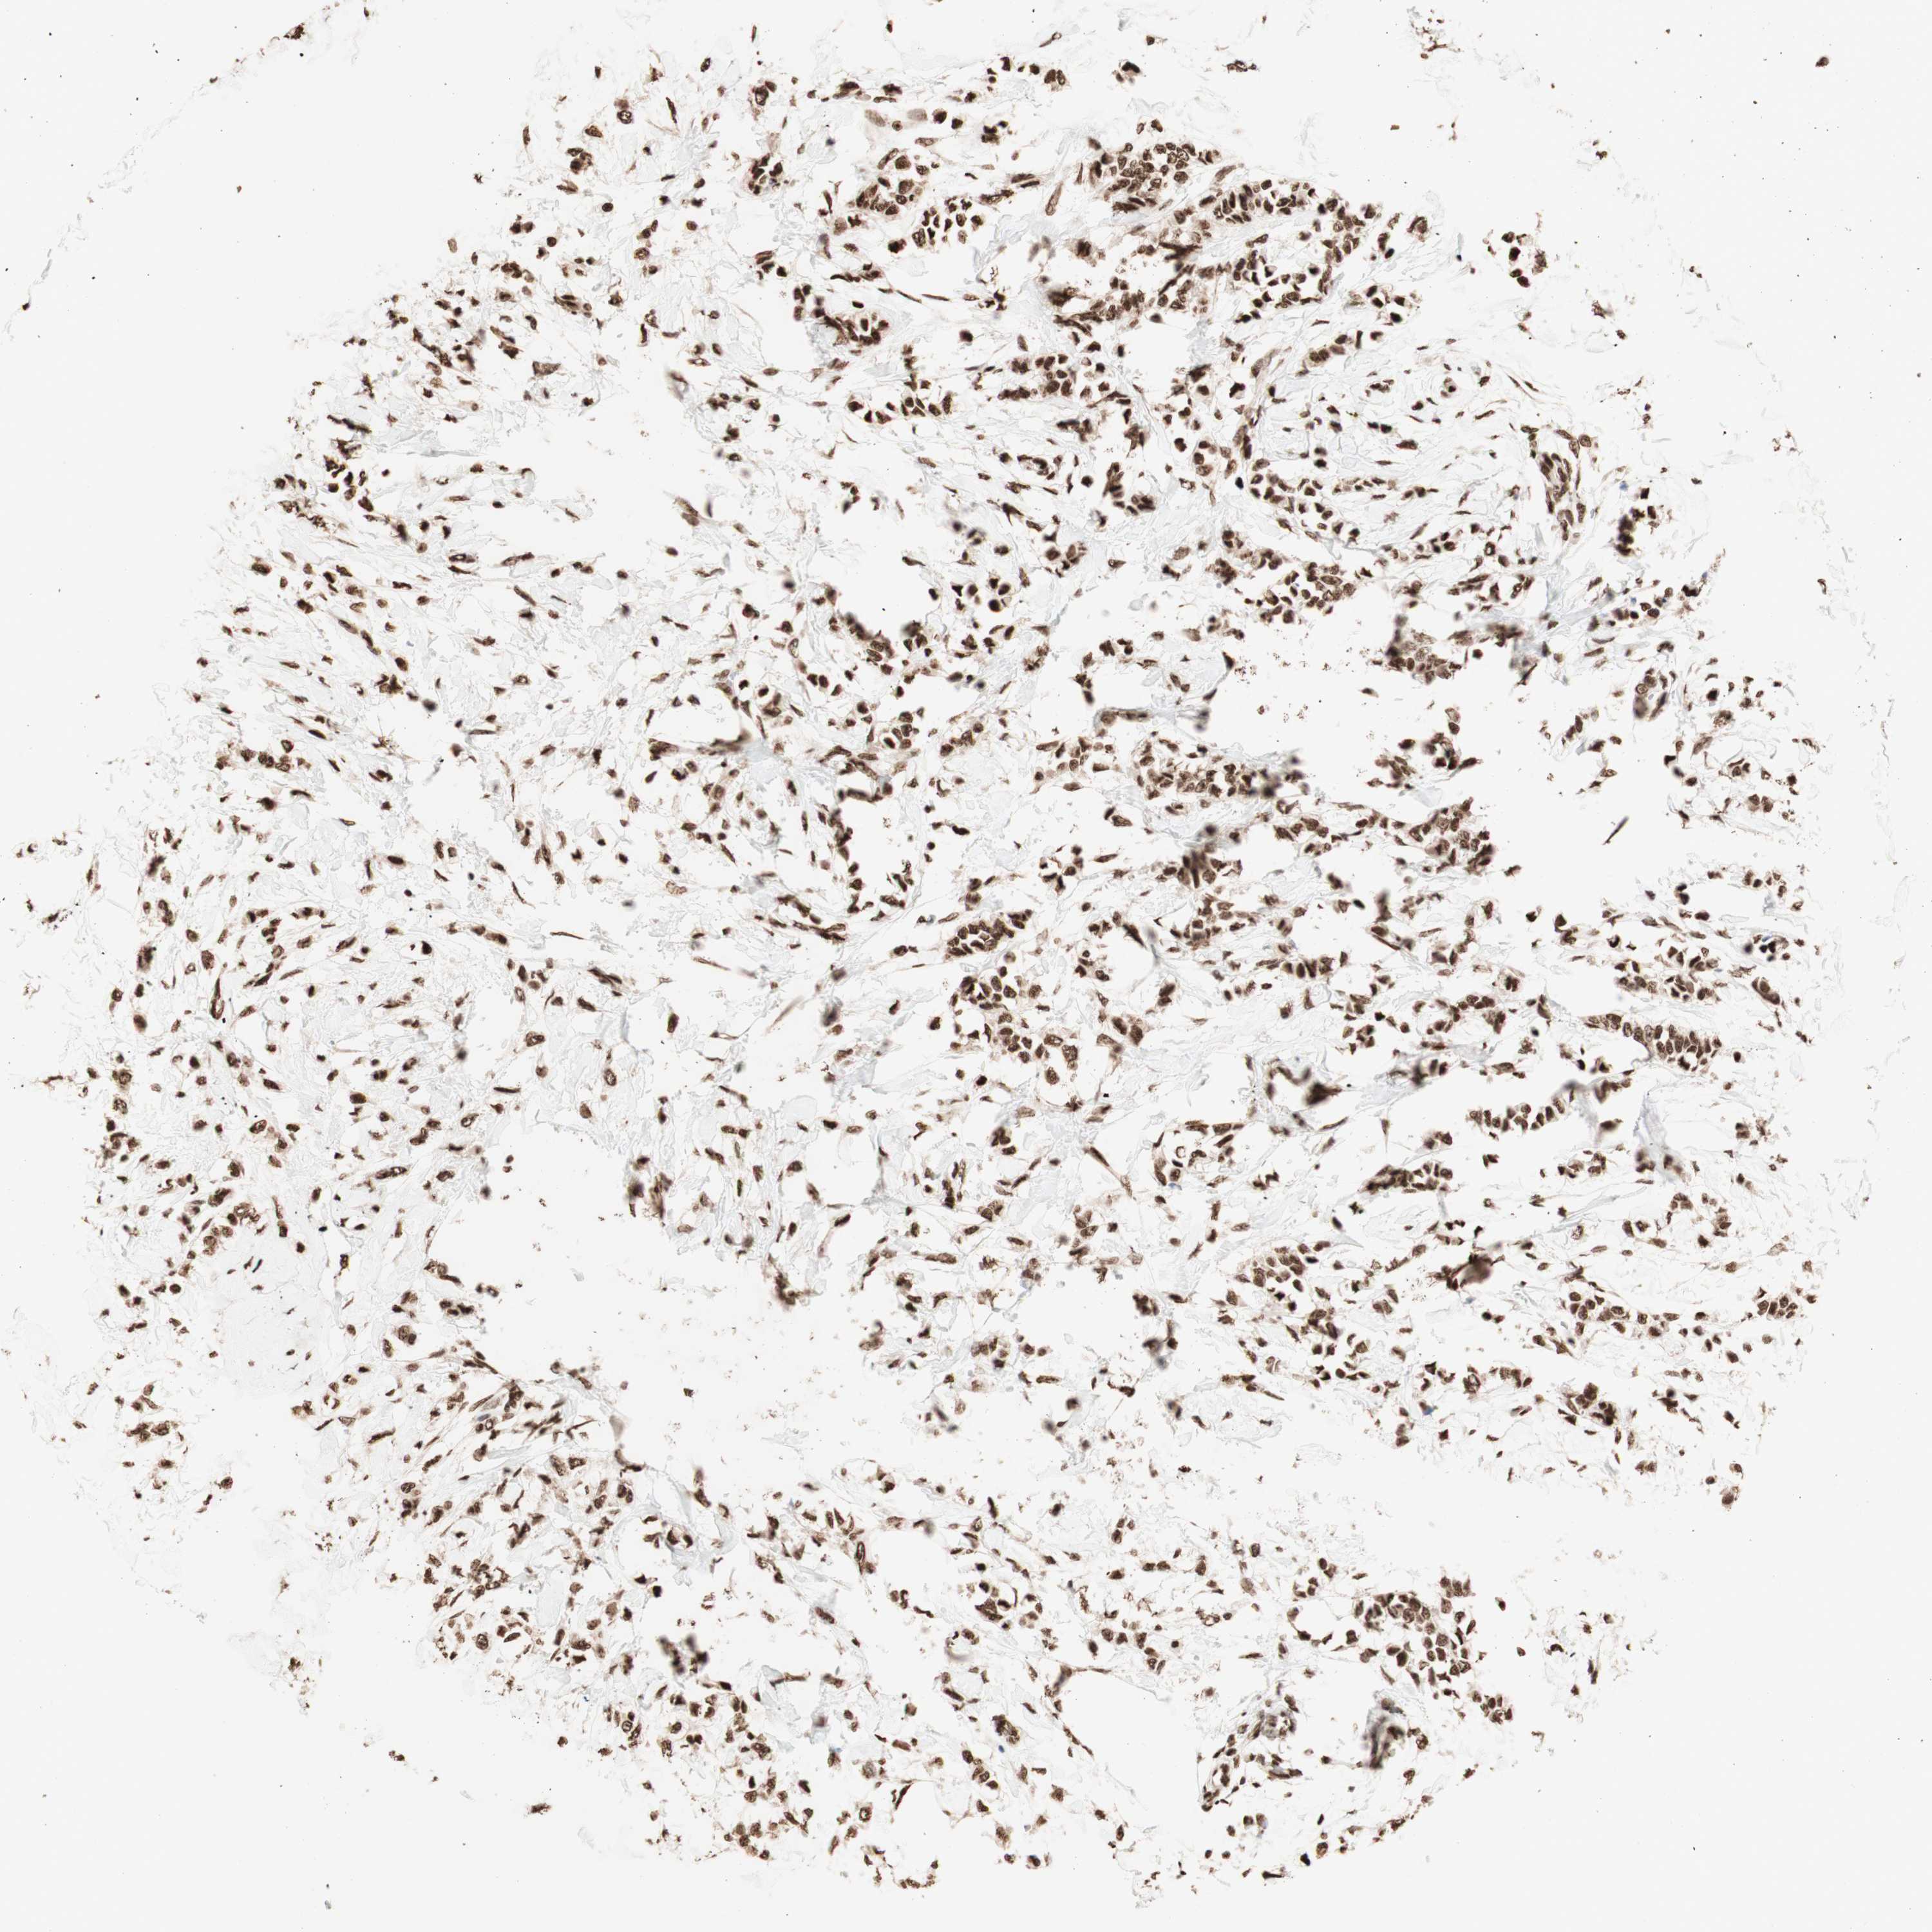

CANCER BREAST CANCER Show tissue menu

BRCA TCGA BRCA VALIDATION PROTEIN EXPRESSION